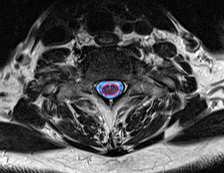

Φυσιολογικός ευρύς σπονδυλικός σωλήνας χωρίς πίεση στο νωτιαίο μυελό (κόκκινο περίγραμμα. |